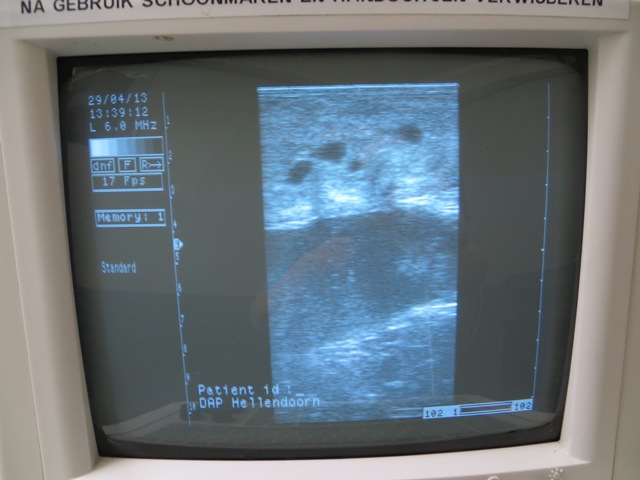

Uiteindelijk kan de dierenarts aan de hand van rectaal onderzoek met behulp van echografie inschatten hoe de baarmoeder en eierstokken er aan toe zijn en een advies geven omtrent het gebruikt van welke vorm van sperma (vers, diepvries, onverdund). Ook kent de dierenarts vaak de voorgeschiedenis van de merrie (wel of niet altijd makkelijk drachtig geworden, al dan niet aan de nageboorte gestaan, al dan niet vochtophopingen in de baarmoeder gehad, baarmoedermond problemen, etc etc). Deze zaken zijn ook zeker van belang bij het advies.